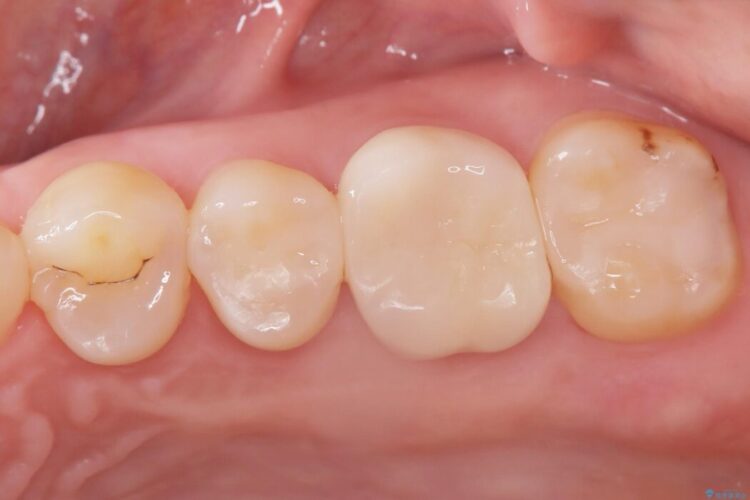

詰め物内部の虫歯治療、隠れた根管の発見

詰め物内部の虫歯治療、隠れた根管の発見 ビフォー 詰め物内部の虫歯治療、隠れた根管の発見 アフター

奥歯の詰め物が取れたとご来院された患者様です。